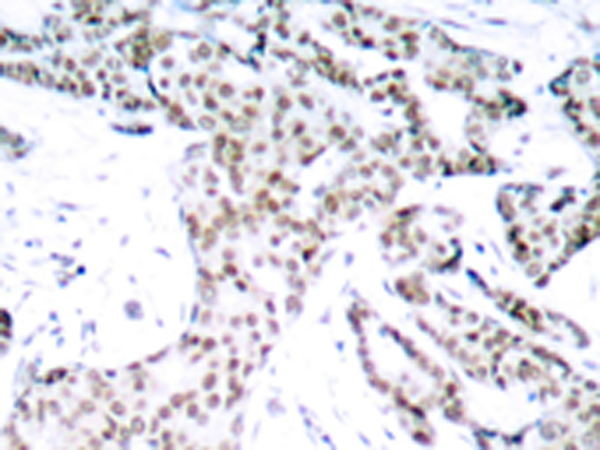

IHC positive control: |

Human breast carcinoma |

IHC Recommend dilution: |

50-100 |